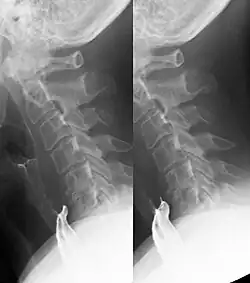

Zervikaler ösophagealer Pouch

Ein zervikaler ösophagealer Pouch ist eine vorübergehende kleine Ausstülpung der Speiseröhre während des Schluckens am häufigsten nach hinten unmittelbar unter dem oberen Ösophagussphinkter im Laimer-Dreieck. Wenn die Ausstülpung auch in der Ruhephase zwischen dem Schlucken konstant nachweisbar ist, handelt es sich um ein Killian-Jamieson-Divertikel.

Die Lage unter dem Sphinkter und dadurch bedingt die Entleerung nach unten in die Speiseröhre helfen bei der Abgrenzung gegen Zenker-Divertikel und -pouches.